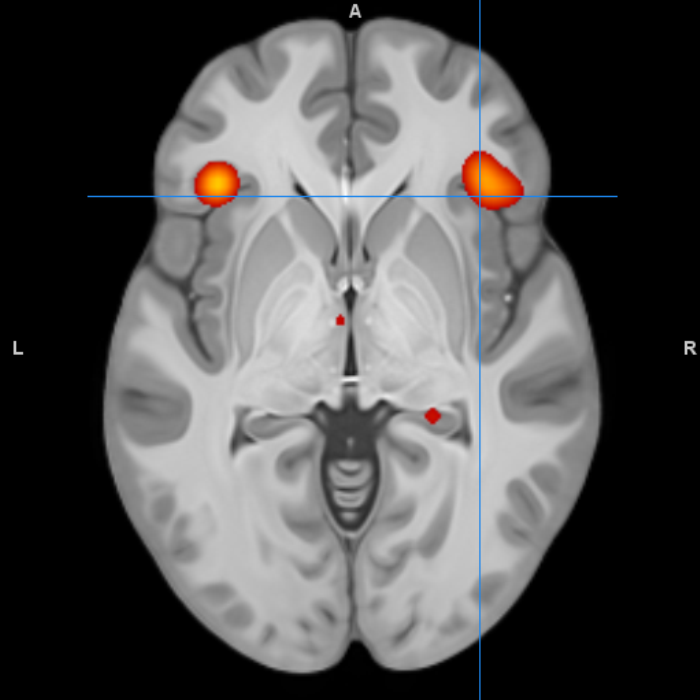

brain scan

Cognitive and Clinical Neuroscience - Fundamental and applied research into brain function using techniques such as functional magnetic resonance imaging (fMRI), electroencephalography (EEG), electromyography (EMG), eye-tracking, transcranial magnetic stimulation (TMS), transcranial direct-current stimulation (tDCS), infrared thermography together with psychophysics and cognitive behavioural paradigms in health and disease.